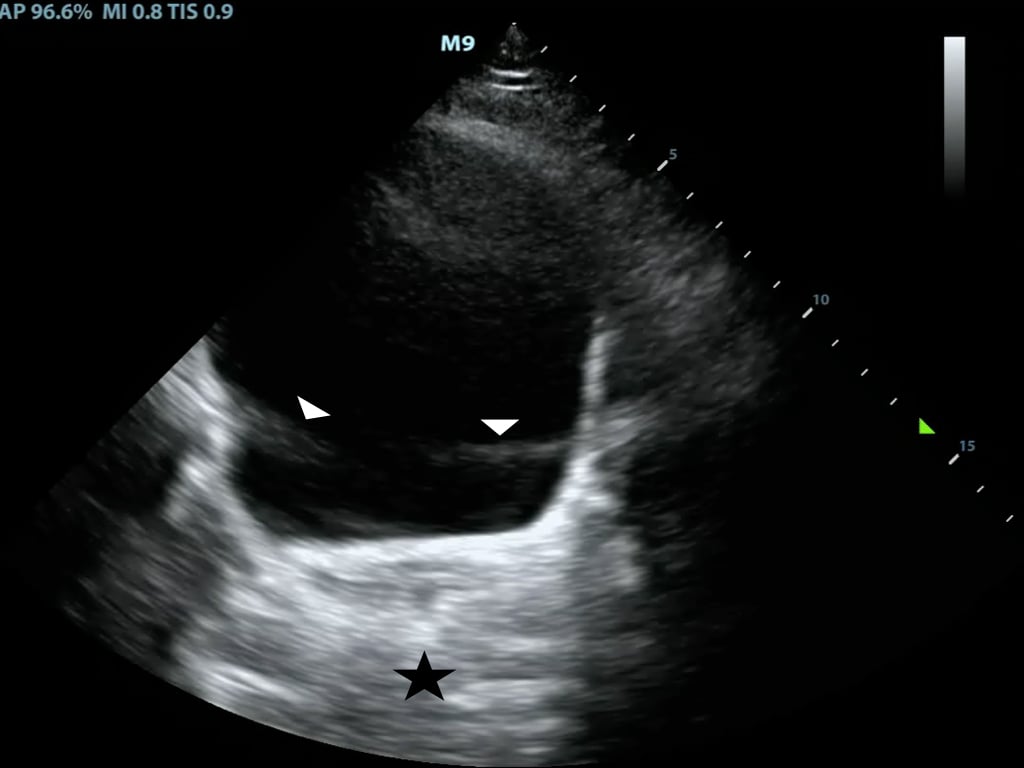

- B-mode or ‘brightness mode’ provides structural information utilizing different shades of gray (or different ‘brightness’) in a two-dimensional image (Figure 1)

- Figure 1. B-Mode image of free fluid in the right upper quadrant

- Brightness is determined by the amplitude of returning echoes

- Anechoic/Echolucent – Complete or near absence of returning sound waves, area is black

- Hypoechoic - Structure has very few echoes and appears darker than surrounding tissue

- Hyperechoic/Echogenic – Large amplitude of returning echoes appears brighter than surrounding tissue

- M-mode (motion mode) captures returning echoes in only one line of the B-mode image displayed over time

- Movement of structures positioned in that line can now be visualized

- Often M-mode and B-mode are displayed together in real-time on the ultrasound monitor (Figure 2, Video 1)

- Figure 2. M-Mode (lower portion of the image) combined with B-Mode image. In this still image the M-mode captures the movement of a particular part of the heart.)

Video 1. M-Mode showing movement of the mitral valve